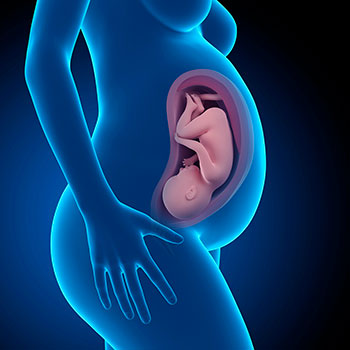

Na 38ª semana de gravidez, o peso do teu filho ultrapassa os 3 Kg, enquanto o seu comprimento se mantém à volta dos 48,6 cm.

Grávida de 38 semanas

A capa de gordura que o cobre tende, em parte, a desfazer-se e a ficar em suspensão no líquido amniótico: a sua pele agora sente com maior intensidade a sensação da água que o envolve.

Nesta semana, entras na “zona de parto”, mas alguns bebés podem ainda demorar quatro semanas.

Idade do feto: 36 semanas.